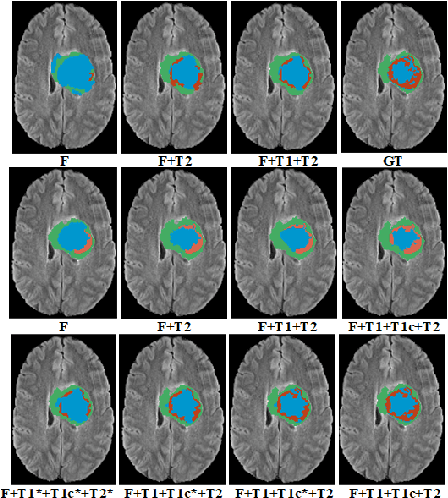

Abstract:Magnetic resonance imaging (MRI) provides varying tissue contrast images of internal organs based on a strong magnetic field. Despite the non-invasive advantage of MRI in frequent imaging, the low contrast MR images in the target area make tissue segmentation a challenging problem. This paper demonstrates the potential benefits of image-to-image translation techniques to generate synthetic high tissue contrast (HTC) images. Notably, we adopt a new cycle generative adversarial network (CycleGAN) with an attention mechanism to increase the contrast within underlying tissues. The attention block, as well as training on HTC images, guides our model to converge on certain tissues. To increase the resolution of HTC images, we employ multi-stage architecture to focus on one particular tissue as a foreground and filter out the irrelevant background in each stage. This multi-stage structure also alleviates the common artifacts of the synthetic images by decreasing the gap between source and target domains. We show the application of our method for synthesizing HTC images on brain MR scans, including glioma tumor. We also employ HTC MR images in both the end-to-end and two-stage segmentation structure to confirm the effectiveness of these images. The experiments over three competitive segmentation baselines on BraTS 2018 dataset indicate that incorporating the synthetic HTC images in the multi-modal segmentation framework improves the average Dice scores 0.8%, 0.6%, and 0.5% on the whole tumor, tumor core, and enhancing tumor, respectively, while eliminating one real MRI sequence from the segmentation procedure.

Abstract:The magnetic resonance (MR) analysis of brain tumors is widely used for diagnosis and examination of tumor subregions. The overlapping area among the intensity distribution of healthy, enhancing, non-enhancing, and edema region makes the automatic segmentation a challenging task. Here, we show that a convolutional neural network trained on high-contrast images can transform intensity distribution of brain lesion in its internal subregions. Specifically, generative adversarial network (GAN) is extended to synthesize high-contrast images. A comparison of these synthetic images and real images of brain tumor tissue in MR scans showed significant segmentation improvement and decreased the number of real channels for segmentation. The synthetic images are used as a substitute for real channels and can bypass real modalities in the multimodal brain tumor segmentation framework. Segmentation results on BraTS 2019 dataset demonstrate that our proposed approach can efficiently segment the tumor areas.